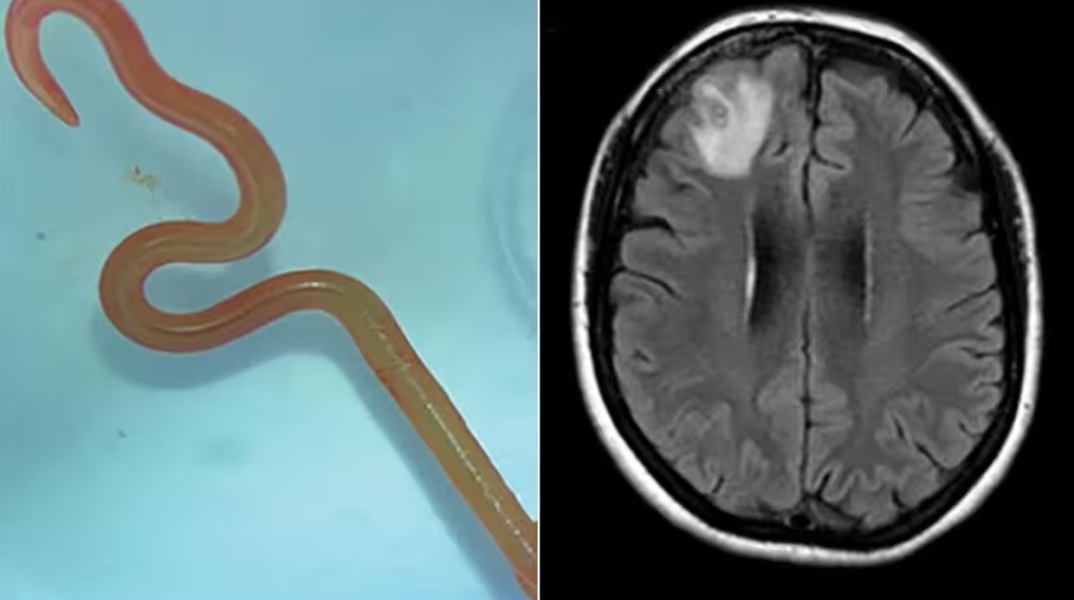

Η νευροχειρουργός Hari Priya Bandi, είχε βγάλει ένα παρασιτικό σκουλήκι μήκους 8 εκατοστών από τον ασθενή της, με αποτέλεσμα να καλέσει τον Senanayake και άλλους συναδέλφους του νοσοκομείου για συμβουλές σχετικά με το τι να κάνει στη συνέχεια.

Μια μαγνητική τομογραφία του εγκεφάλου της αποκάλυψε ανωμαλίες που απαιτούσαν χειρουργική επέμβαση.

Το Ophidascaris robertsi είναι ένα στρογγυλό σκουλήκι που συναντάται συνήθως σε πύθωνες. Η ασθενής του νοσοκομείου της Καμπέρα σηματοδοτεί την πρώτη παγκοσμίως περίπτωση εντοπισμού του παρασίτου σε ανθρώπους.